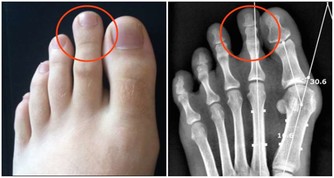

腎:怕肉

經常大魚大肉,容易導致蛋白質攝入超標,長期如此會增加腎臟負擔。腎臟不好的患者,如果繼續多吃肉,更會加重對腎臟的損害。